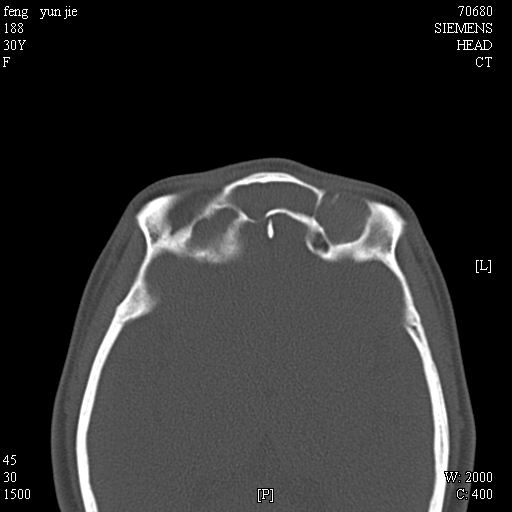

女,37岁,多年前鼻骨骨折过,现在穿刺有炎性分泌物

考虑:1、鼻骨陈旧性骨折;

2、额窦粘液囊肿(右侧水平额窦突入眶内上方)可能性大。

1)左侧鼻骨骨折(陈旧性)。2)双侧额窦及双侧筛窦炎症,伴右侧额筛窦黏液囊肿突入右侧眼眶。